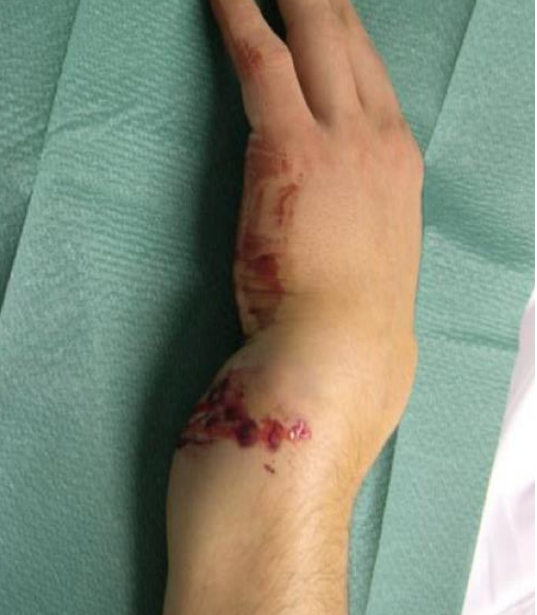

two significant findings

what are the management priorities?

A

• grossly deformed swollen left wrist consistent with distal radial +/- ulna fracture

• dorsal angulation distal radius

• skin breech and bleeding

**Management **

1. analgesia

2. assess for nerve damage

3. ‘urgent reducion

4. iv abx

5. tetanus

6. POP and post reducion imaging

7. ortho referral